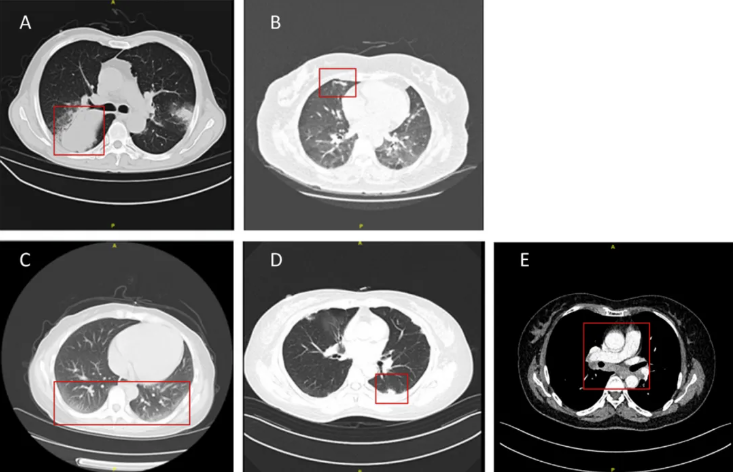

惠普尔养障体阳性患者的影像学表现呈现多样化特征,其中最常见的类型依次为结节(54%)、斑片影(52%)、磨玻璃影(35%)和肿块(24%)(表4)。肺炎患者的代表性影像学表现总结于图3。这种影像学上的多样性使得该病难以仅凭影像学特征与普通肺炎相鉴别,这也是其易被误诊或漏诊的重要原因之一。

图3 惠普尔养障体肺炎的影像学表现,包括肿块(A)、斑片影(B)、磨玻璃影(C)、结节(D)及纵隔淋巴结肿大(E)。